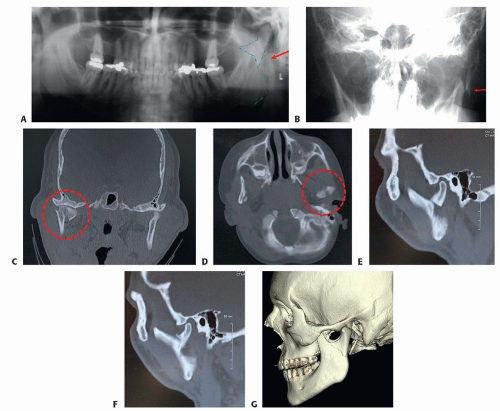

Orthopantomogram is a useful x-ray that identifies most condyle fractures and provides an overview of teeth and bony structures, often giving additional information about occlusion (FIG 4A).

Reverse Towne’s view: This plain film, taken from posterior to anterior with the neck flexed, is a useful adjunct to the panorex to identify condyle fractures (FIG 4B).

CT scans have become the standard for imaging of the maxillofacial skeleton in facial trauma and are indispensable in diagnosing and treatment planning for various types of condyle fractures.